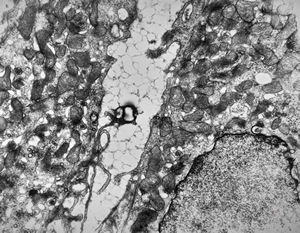

F,52y. | spirochetosis - colon

F,52y. | colon … spirochetosis … subepitheliai microbes